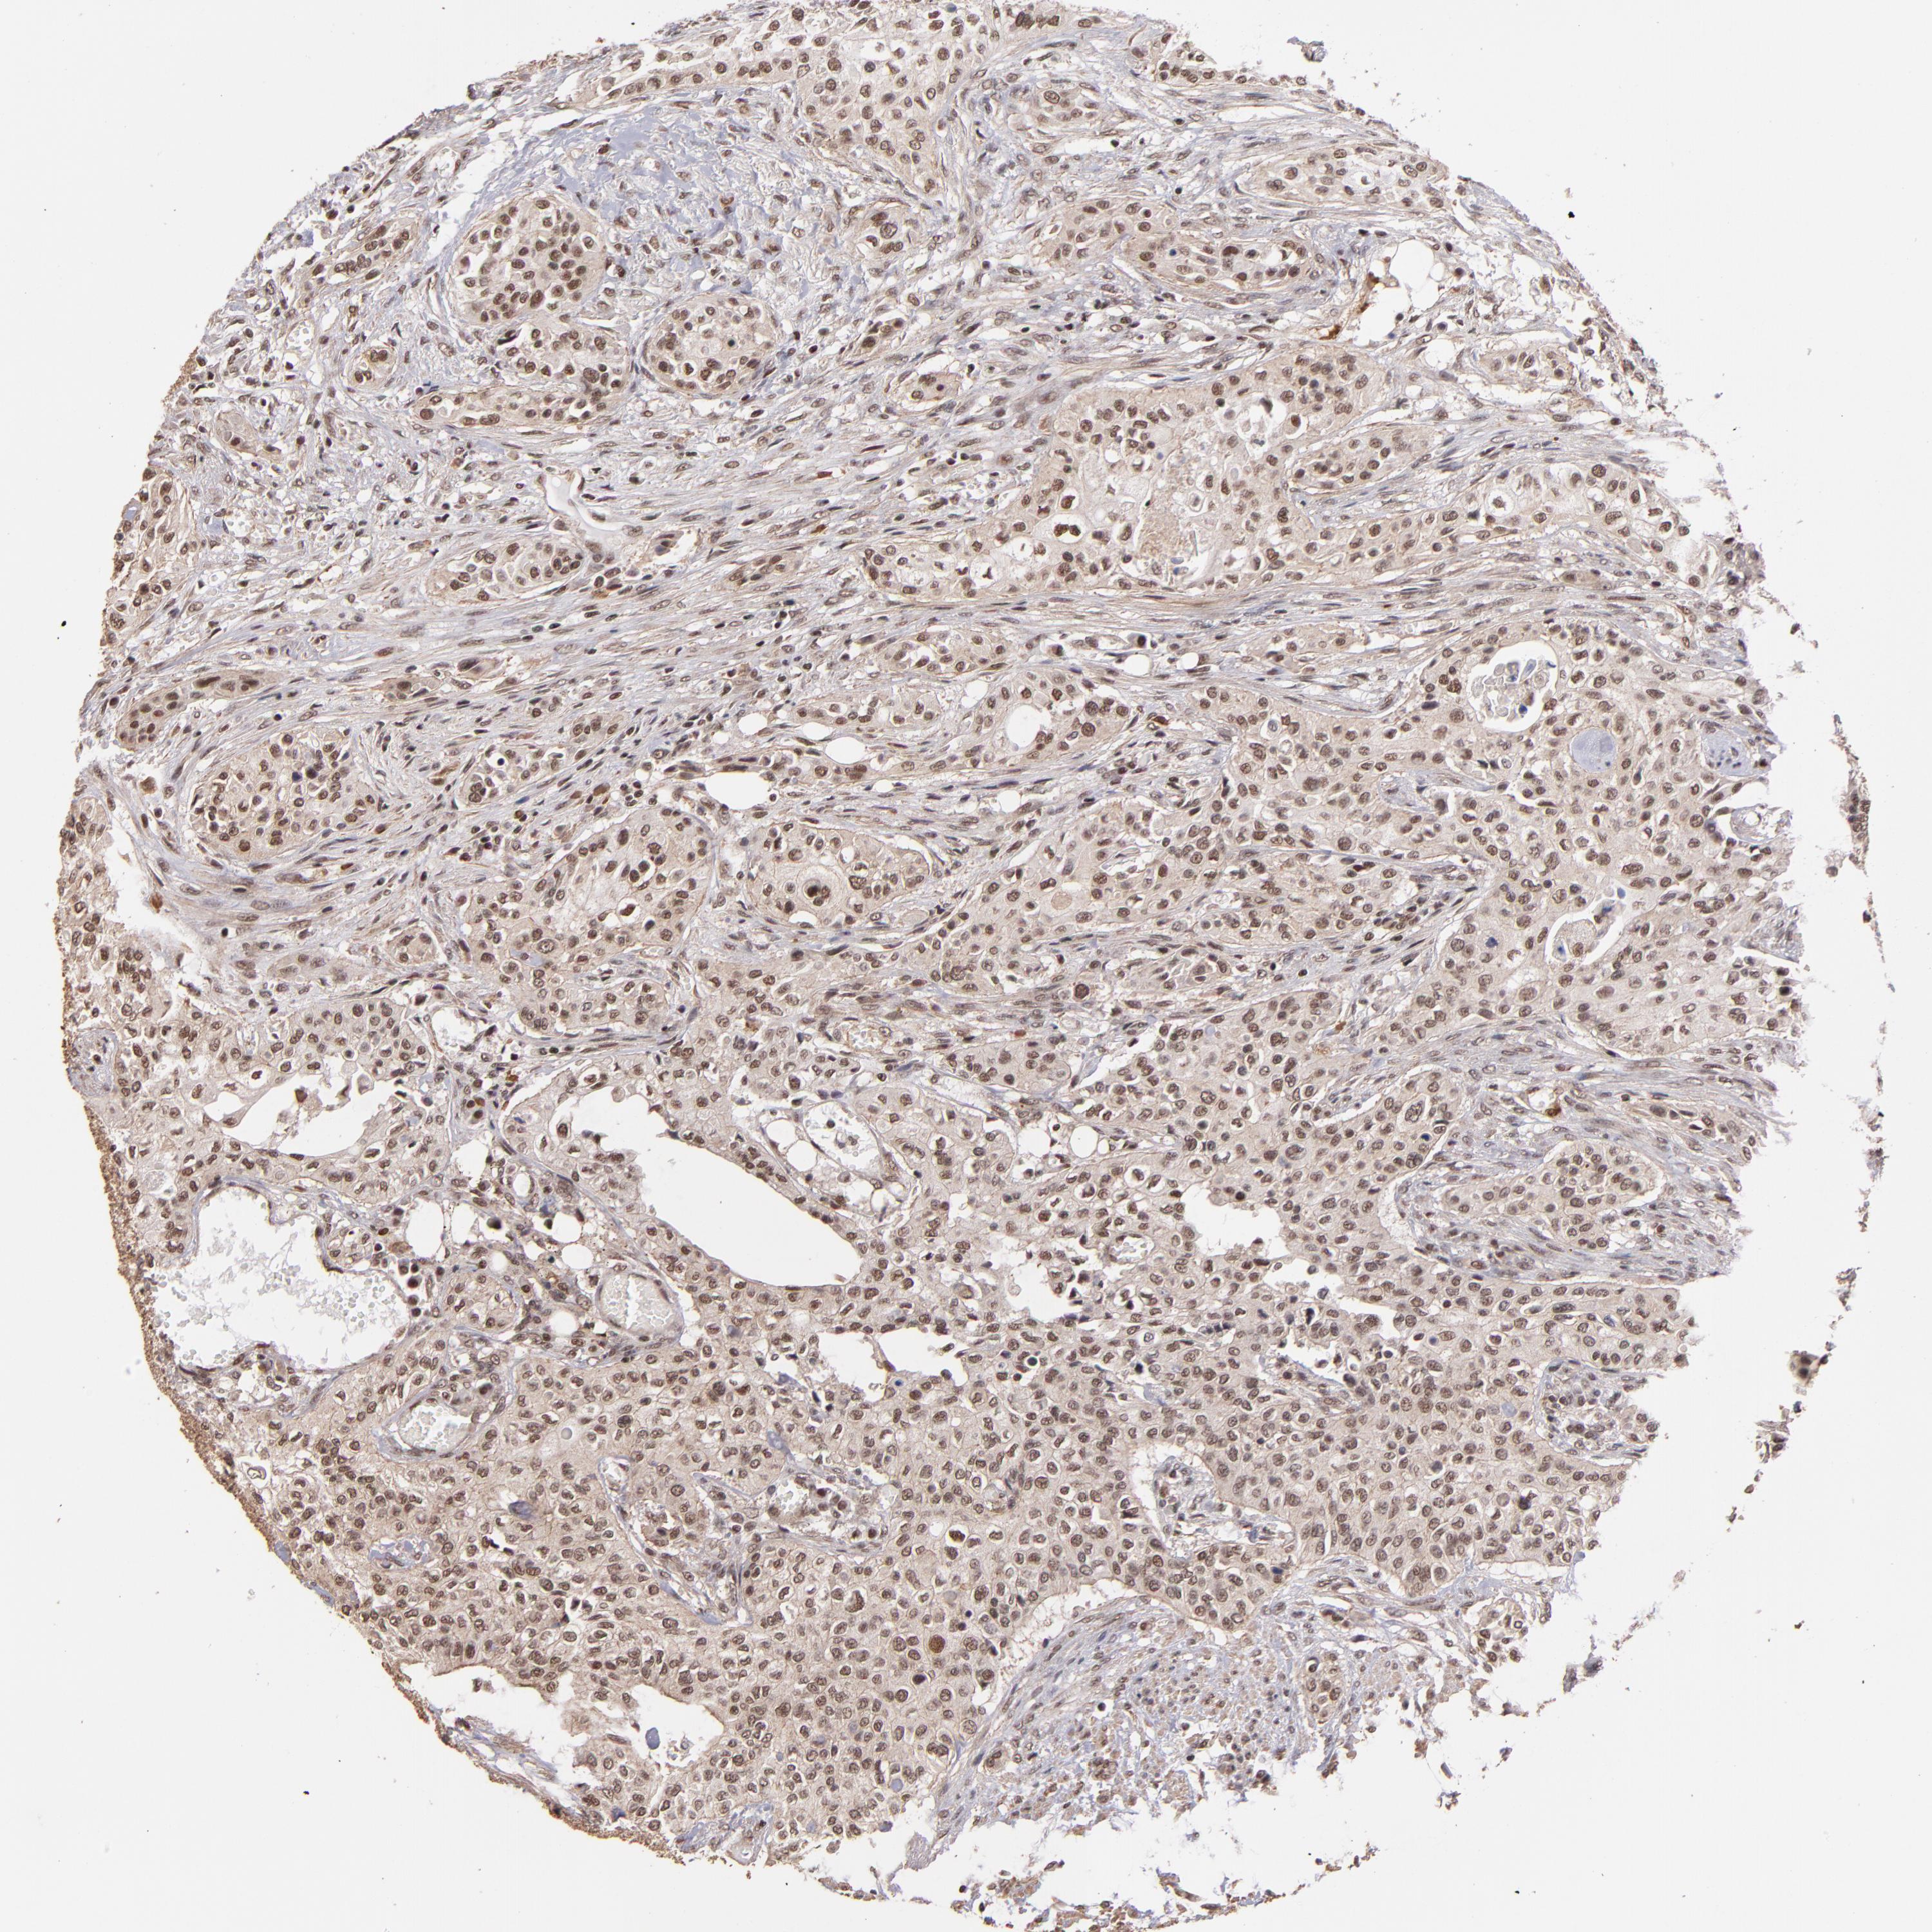

UROTHELIAL CANCER - Protein expressioni

A mouse-over function shows sample information and annotation data. Click on an image to view it in a full screen mode. Samples can be filtered based on level of antibody staining by selecting one or several of the following categories: high, medium, low and not detected. The assay and annotation is described here.

Note that samples used for immunohistochemistry by the Human Protein Atlas do not correspond to samples in the TCGA dataset.

Antibody stainingi

Antibody staining in the annotated cell types in the current human tissue is reported as not detected, low, medium, or high, based on conventional immunohistochemistry profiling in selected tissues. This score is based on the combination of the staining intensity and fraction of stained cells.

Each image is clickable and will lead to virtual microscopy that enables deeper exploration of all samples and also displays staining intensity scores, fraction scores and subcellular localization as well as patient and tissue information for each sample.

Antibody HPA001907

Antibody HPA002735

Antibody CAB010451

Antibody CAB080271

Staining

High

Medium

Low

Not detected

Intensity

Strong

Moderate

Weak

Negative

Quantity

>75%

75%-25%

<25%

None

Location

Nuclear

Cytoplasmic/membranous

Cytoplasmic/membranous,nuclear

Urothelial carcinoma, High grade

Urothelial carcinoma, Low grade

Adenocarcinoma, NOS